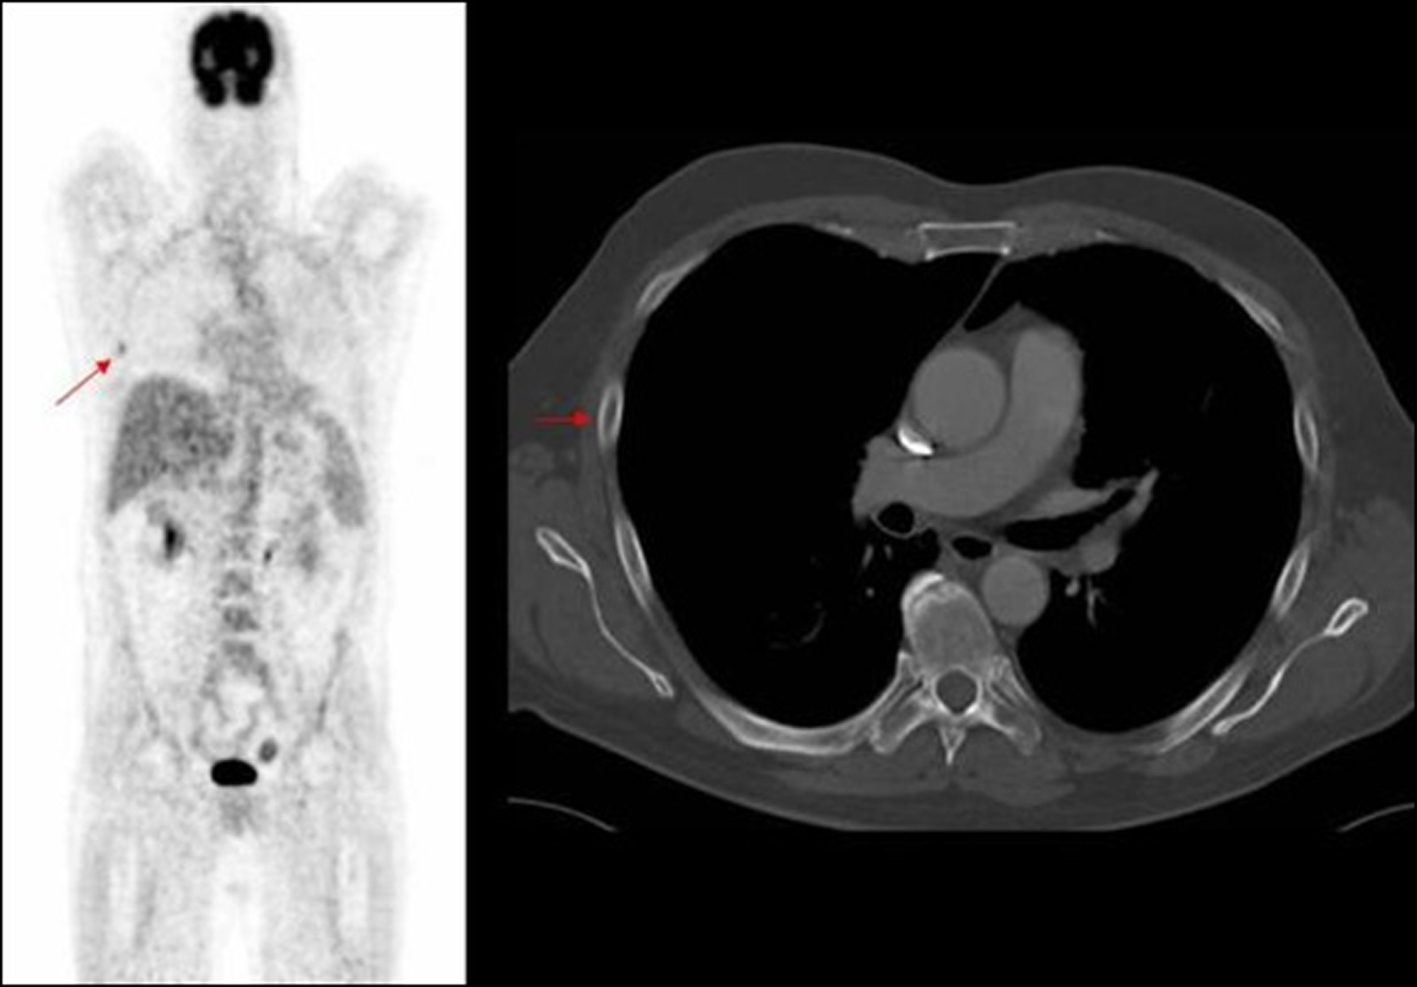

In our study nearly half of the in field metastasis were identified by two observers (Fig. 1). Most of the missed in field metastasis were bony involving the ribs, acromion and spine (Fig. 2, 3, 4). This could be explained by a number of reasons. Firstly it is easier to overlook a small bony metastasis especially in the ribs. Secondly, MIP (maximum intensity projection) reconstructions helps to depict the metastatic deposits better. If one does not routinely perform these, it might account for the missed deposits.

![]() Click for large image | Figure 4. PET image of rib deposit initially noted in PET, not identified on corresponding axial CT image. |